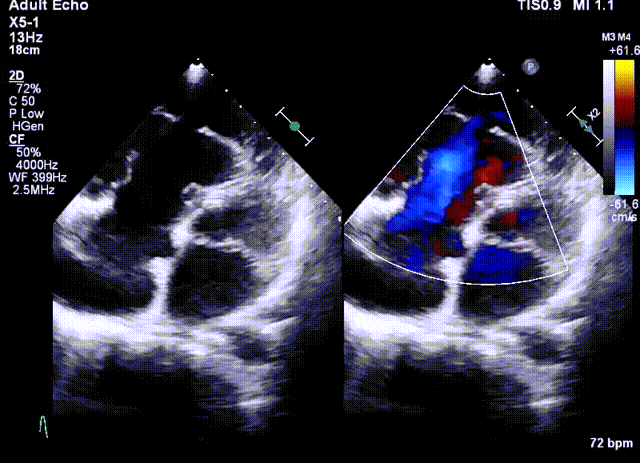

術(shù)前超聲